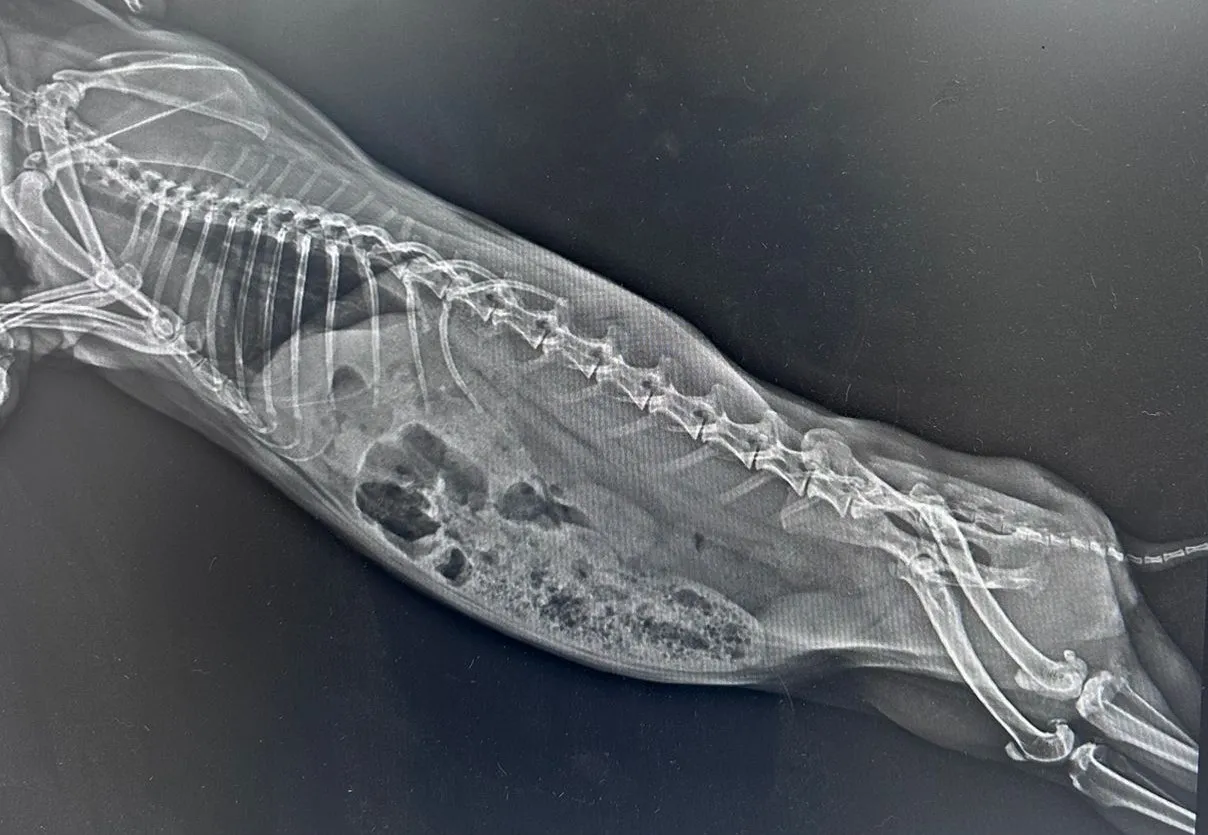

Kliniğimizde

-Röntgen (50Ma)